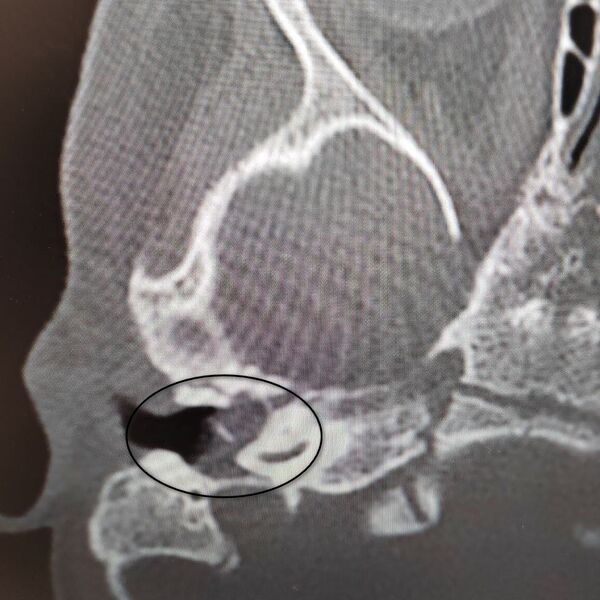

Девочка поступила в оториноларингологическое отделение больницы с хроническим гнойным средним отитом и подозрением на врожденную холестеатому барабанной полости — кистозное патологическое образование в среднем ухе. Врачи отметили, что подобное заболевание крайне редко диагностируется у детей в столь раннем возрасте.

«Холестеатома опасна тем, что может привести к рецидивирующему гноетечению и разрушению структур среднего уха, отвечающих за слух», — пояснили в пресс-службе ведомства.

После обследования и подтверждения диагноза пациентку направили на операцию, в ходе которой хирурги удалили у нее холестеатому, провели декомпрессию лицевого нерва и восстановили механизм звукопроведения.